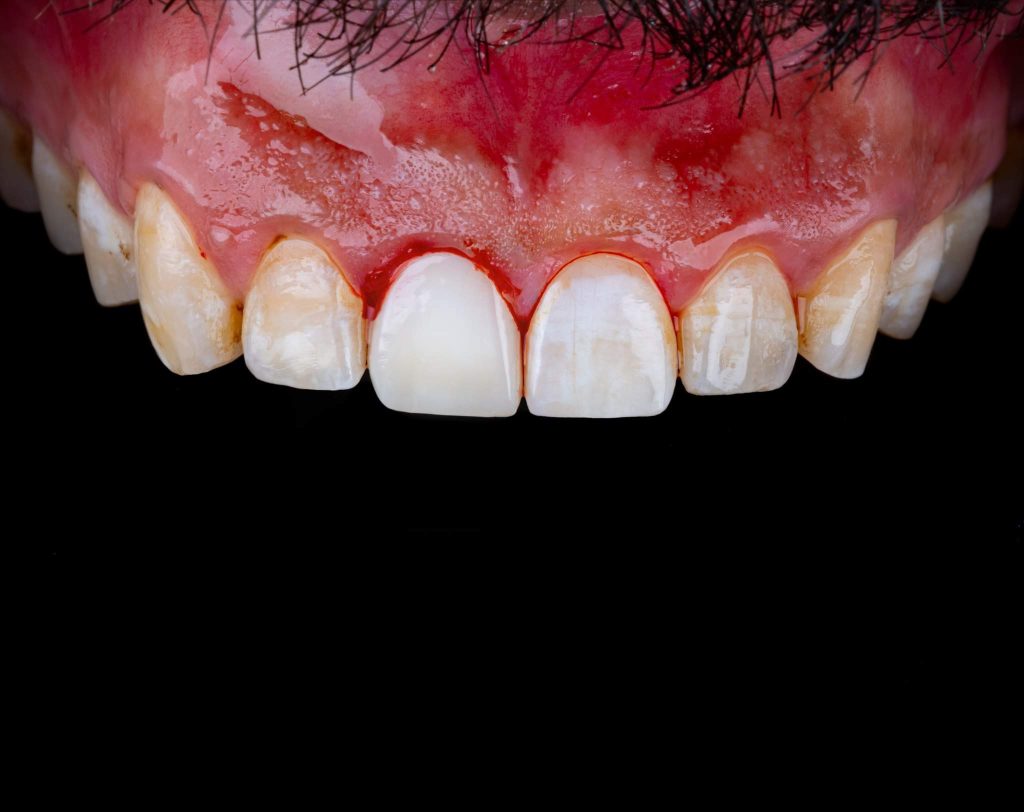

This is a case of discolored right central incisor for a 21 years-old-male patient. He had a history of previous trauma 2 years ago to his tooth and fracture, that was managed with a composite restoration. After clinical examination and x-ray imaging, the tooth was non-vital with periapical lesion.

After discussing the treatment options with the patient, he chose the direct composite veneer. The treatment included endodontic treatment, internal bleaching, direct composite veneer for the right central, and aesthetic reshaping for the laterals and left incisor also by composite restoration. The case completed in 2 sessions.